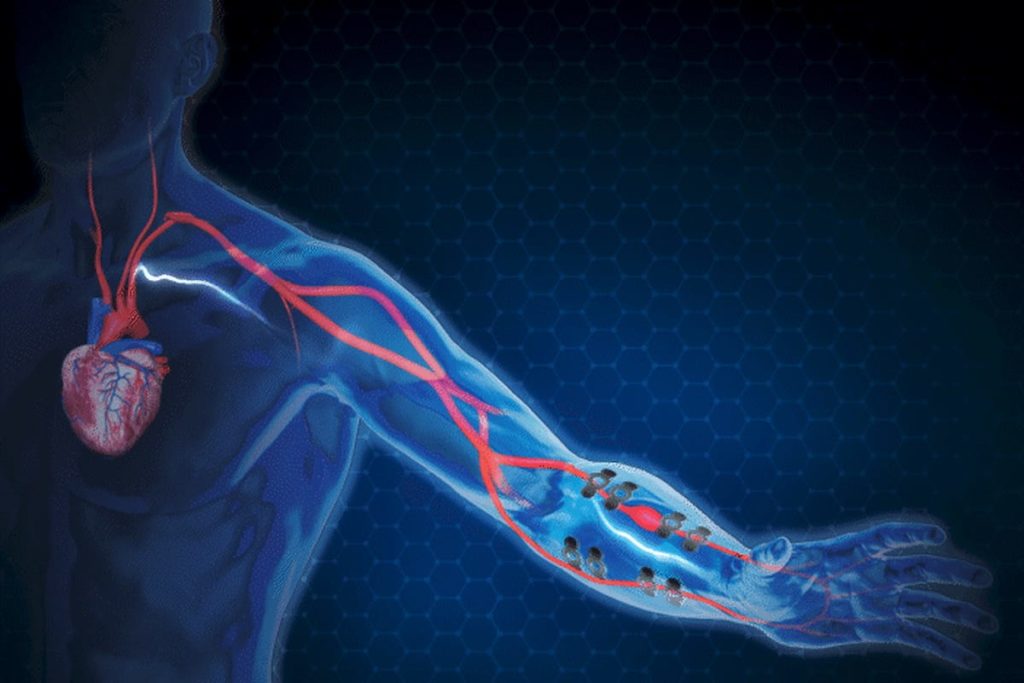

Ученые создали ИИ-тату, отслеживающее артериальное давление

Американские ученые разработали ИИ-татуировку для отслеживания артериального давления.

Растяжимая электронная наклейка на базе графеновых датчиков подает в кожу слабый электрический ток и анализирует реакцию организма. Распространение сигнала по пути наименьшего сопротивления позволяет определить изменения биоимпеданса, коррелирующие с динамикой артериального давления.

Исследователи также научили устройство измерять скорость пульсовых волн. Они использовали эти сведения вместе с данными биоимпеданса для тренировки ИИ прогнозированию точек диастолического и систолического артериального давления.

Ученые привлекли семь добровольцев, чтобы собрать 18 667 записей. Из них 89% пошли на обучение алгоритма, а 11% — на его тестирование.

По данным ученых, точность измерения устройства составила 0,2±4,5 мм рт. ст. для диастолического давления и 0,2±5,8 мм рт. ст. для систолического, что эквивалентно классу А стандарта IEEE для устройств мониторинга артериального давления.